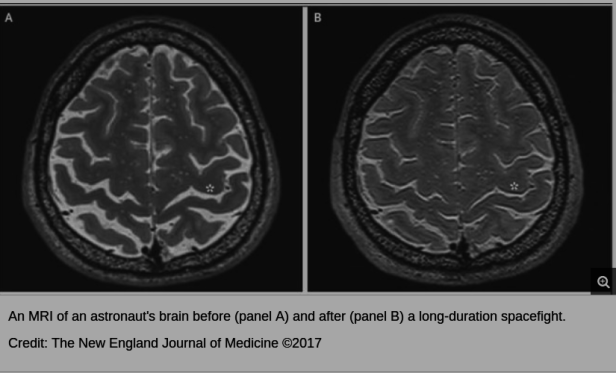

IF astronauts do succeed in the long trek to Mars, will they by then have enough intelligence left to actually operate the nuclear reactor, given that scientists have found that space travel damages astronauts’ brains?The Kilopower project is working to advance a design for a compact, low-cost, and scalable nuclear fission power system for missions that require lots of power, such as a human mission to Mars. The technology uses a fission reactor with a uranium-235 reactor core to generate heat, which is then transferred via passive sodium heat pipes to Stirling engines. Those engines use that heat to create pressure, which moves a piston – much as old coal-powered ships used steam pressure to run their pistons. When coupled to an alternator, the Stirling engine produces electricity.